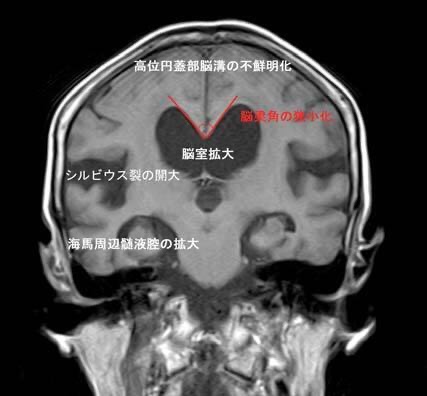

いわゆる治る認知症と言われる疾患ですし、歩行障害を主訴にする場合はこの水頭症、脊椎脊髄疾患とパーキンソン病のような神経疾患と鑑別しないといけません。鑑別する上で重要なポイントで画像検査の時に冠状断(Coronal)スキャンしたものが役立ちます、当院ではルーチン画像に含まれていますが、通常施設だと横断(Axal)スキャンが一般的なので見逃す可能性もあります。

(MRIのCoronal view:国立長寿医療研究センターホームページより転載)